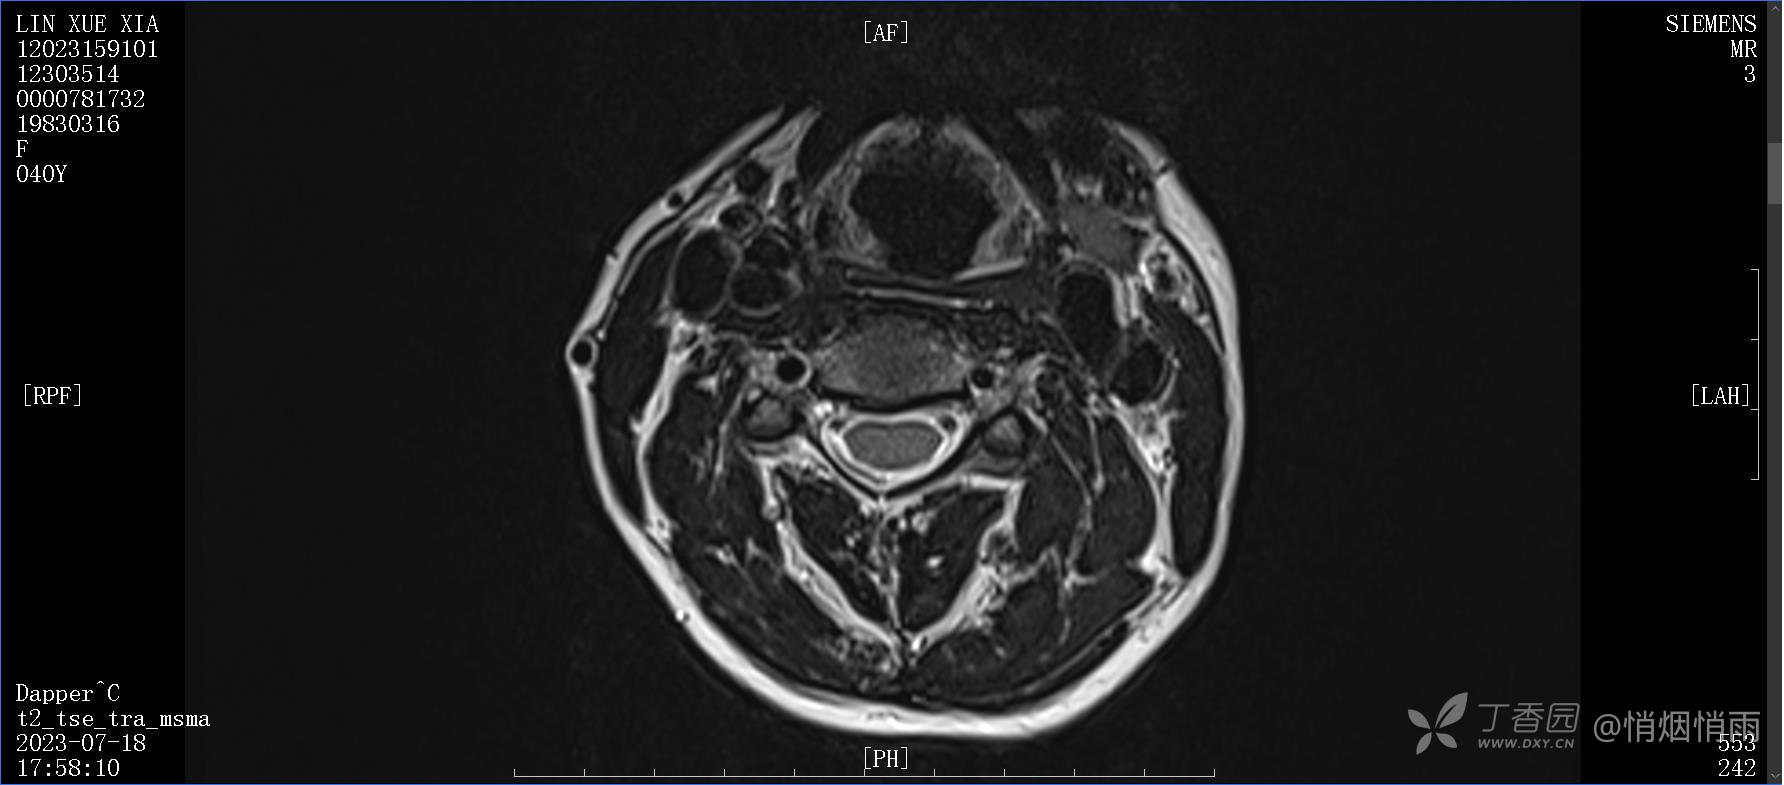

辅助检查:

目前的诊断,暂时依据辅助检查诊为肩袖损伤,但是患者疼痛的性质和特点,却不是单纯的肩袖损伤所致。考虑过胸廓出口综合征,但是该疾病会出现肩胛区的疼痛吗?(由于考虑到费用的问题,没再进行下一步的检查)带状疱疹会有如此的症状吗?